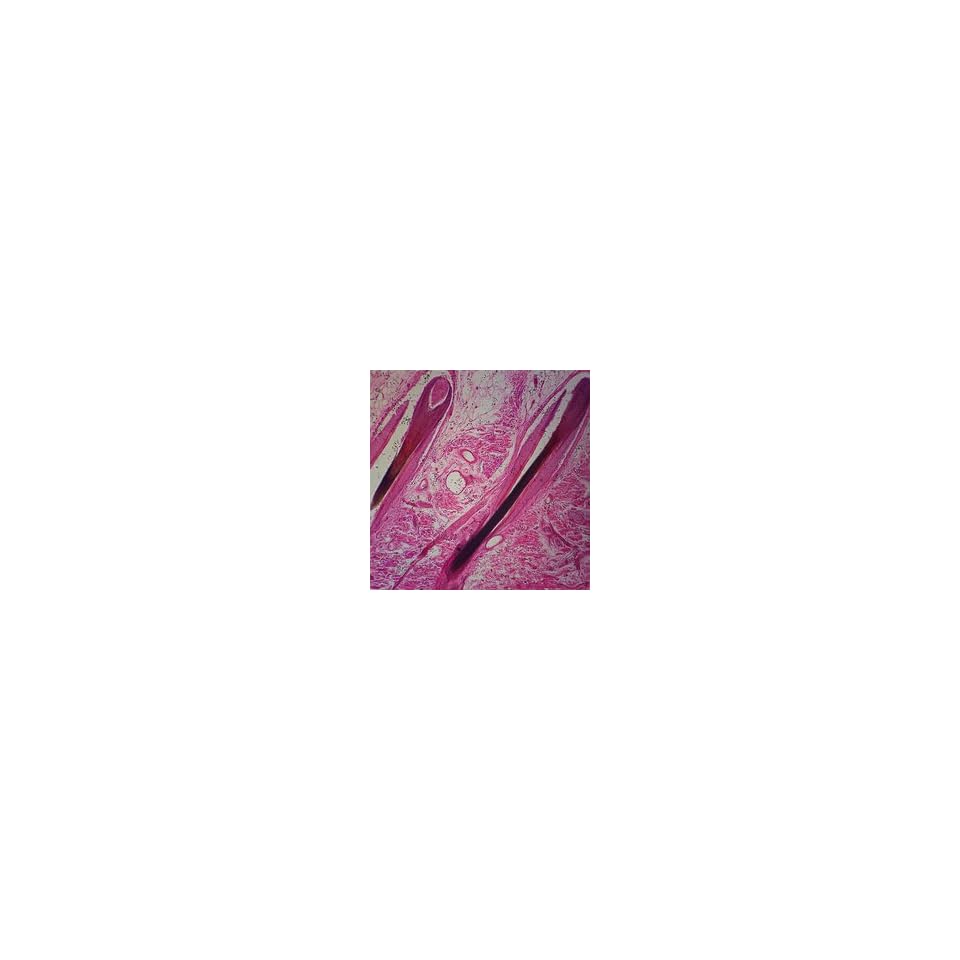

Lieder prepared microscope slides are made in our laboratories under scientific control. Human scalp microscope slide is a section showing portions of hair follicles, sebaceous glands, and sweat glands. The scalp refers to the layers of skin and subcutaneous tissue that cover the bones of cranial vault.

The human scalp and hair microscope slides are microscope slides from 3b scientific and manufactured in germany. Complete with color map and bump maps. The scalp is usually described as having five layers, which can conveniently be remembered as a mnemonic: The scalp consists of five layers, the first three of which are intimately bound together and move as a unit. Human skin scalp prepared microscope slide. So, important microscope slides can be supplied for all students. This model is ready for 3d medical animation/presentation. Human scalp microscope slide is a section showing portions of hair follicles, sebaceous glands, and sweat glands. Lab 4 integumentary, skeletal muscle, joints, radiology, and intro to power lab these pictures of this page are about:human scalp slide. To assist one in memorizing the names of the five layers. It also makes the headset feel a little more floaty (like a nice padded helmet). Lieder prepared microscope slides are made in our laboratories under scientific control. Baillet et al., ieee sig. The human scalp and hair microscope slides are microscope slides from 3b scientific and manufactured in germany. This model is ready for 3d medical animation/presentation. Complete with color map and bump maps. Holly branigan jamie pearson university of edinburgh.